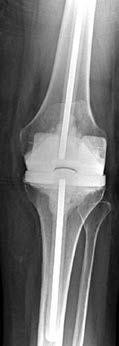

A 65-year-old woman with type 2 diabetes mellitus and hypertension who underwent an index total knee arthroplasty (TKA) 1 year ago has a knee aspirate culture positive methicillin-resistant Staphylococcus aureus periprosthetic joint infection after 2 days of increasing pain and swelling. She states her knee“never felt right.” Her erythrocyte sedimentation rate (ESR) and C-reactive protein (CRP) levels are elevated. Radiographs reveal well-fixed, appropriately positioned components.

What is the most appropriate treatment?

Explanation

This patient has had a painful knee joint since surgery, and it is possible this is a chronic infection. In this setting, a 2-stage reimplantation procedure is most appropriate. There is no role for arthroscopic debridement and resection arthroplasty is not indicated. During the second stage, it is important to obtain cultures to confirm successful eradication of the infection. If there is clinical suspicion for persistent joint infection, an intraoperative frozen section can be indicated, but gram stain is useful. Aspiration and culture prior to the intraoperative culture should be obtained after the patient has not been taking the antibiotic for a minimum of 2 weeks. ESR and CRP trends are more valuable than the actual numbers in this setting. Finally, leukocyte-labeled imaging has no role in this setting.